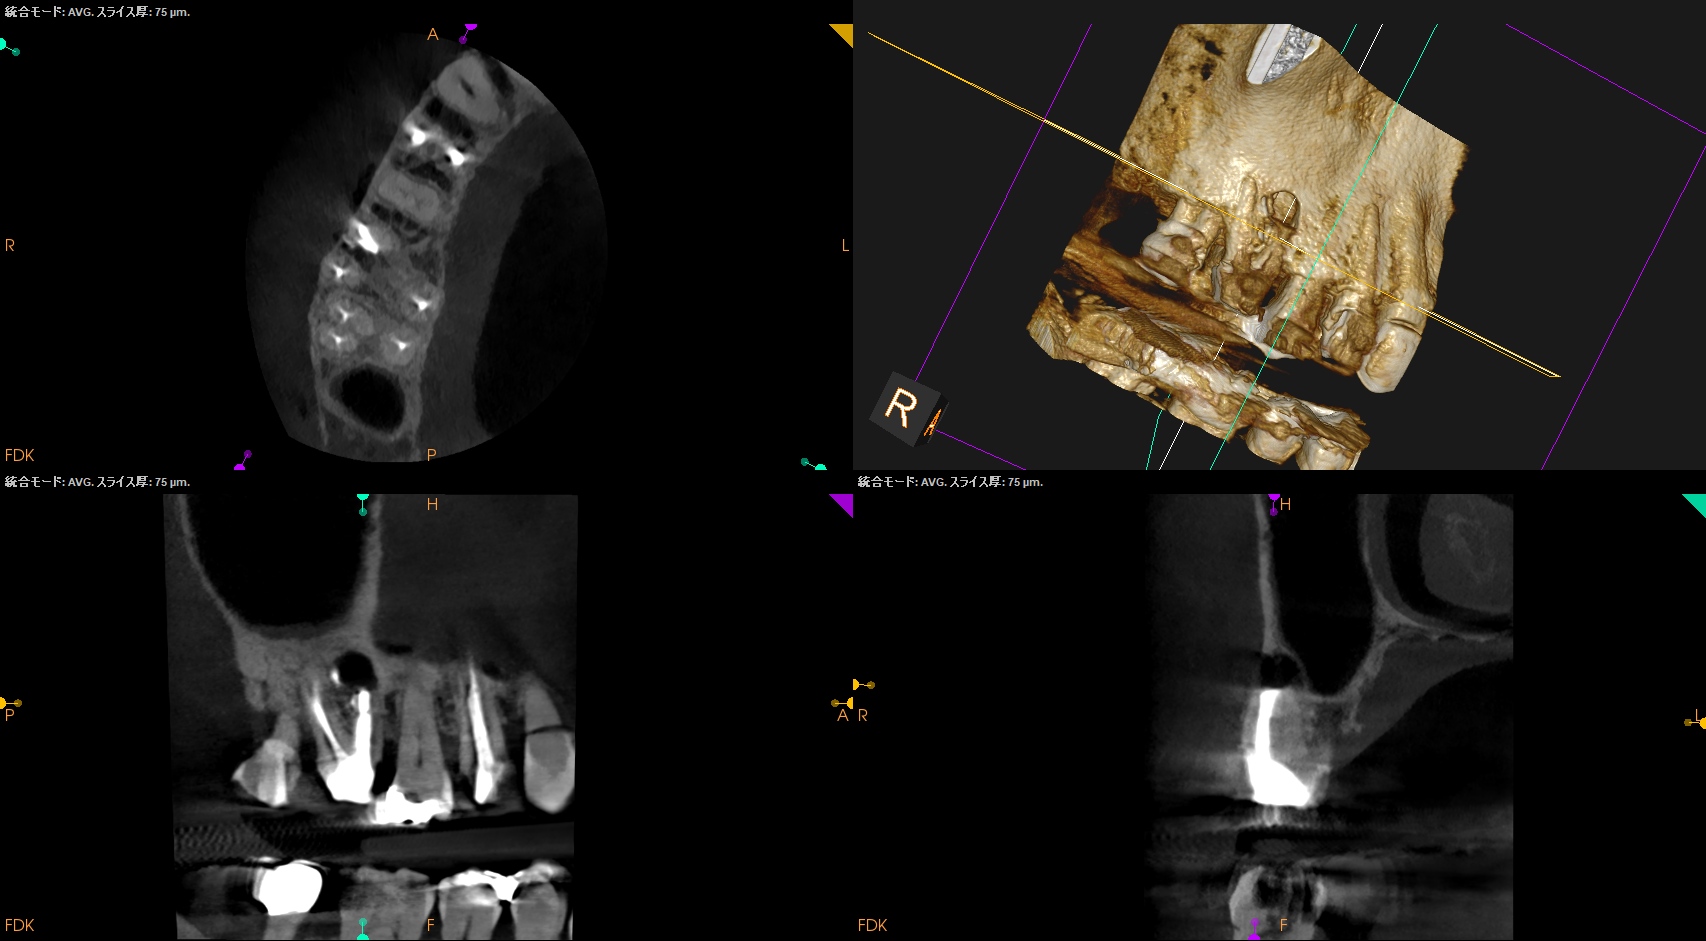

紹介患者さんの治療で、#3 MB Apicoectomyを行ったのだが

MBをRoot resectionした。

ここまでは容易なのだが、この後に逆根管形成・逆根管充填を行うが、

明後日の方向に逆根管形成・逆根管充填してしまう

この状態ではMB2の封鎖がままならない。

その際は、この穿孔部を消去したいので

さらに切断部位から4mm, 頬舌的幅径が6.7mm必要だが再切断し逆根管形成・充填を試みることにした。

人為的にApico-marginal deffectを作らないように注意する必要があるだろう。

Apico-marginal deffectを人為的に作成してしまった。